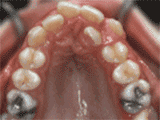

第二種

前牙移位,因?yàn)橛醒例X缺失,導(dǎo)致相鄰牙齒開始沒有秩序的左右移動,經(jīng)過矯正后是這樣的~